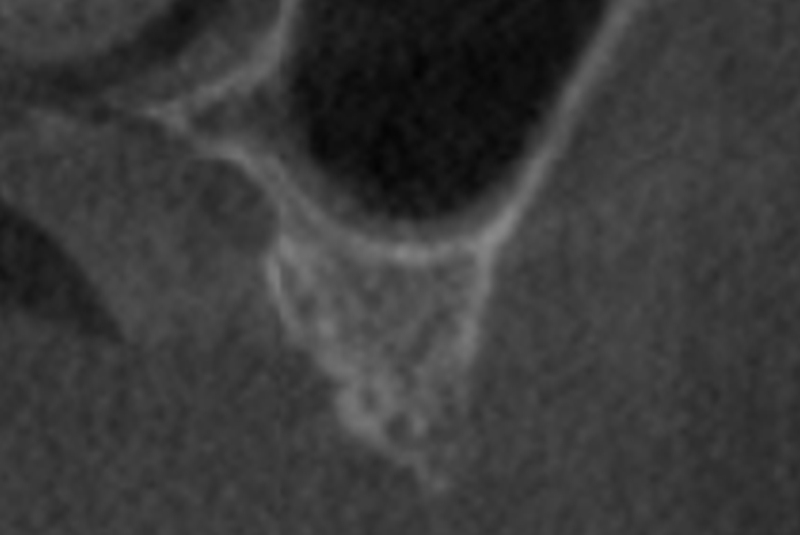

DVT control after sinusitis surgery, residual bone height 1 mm